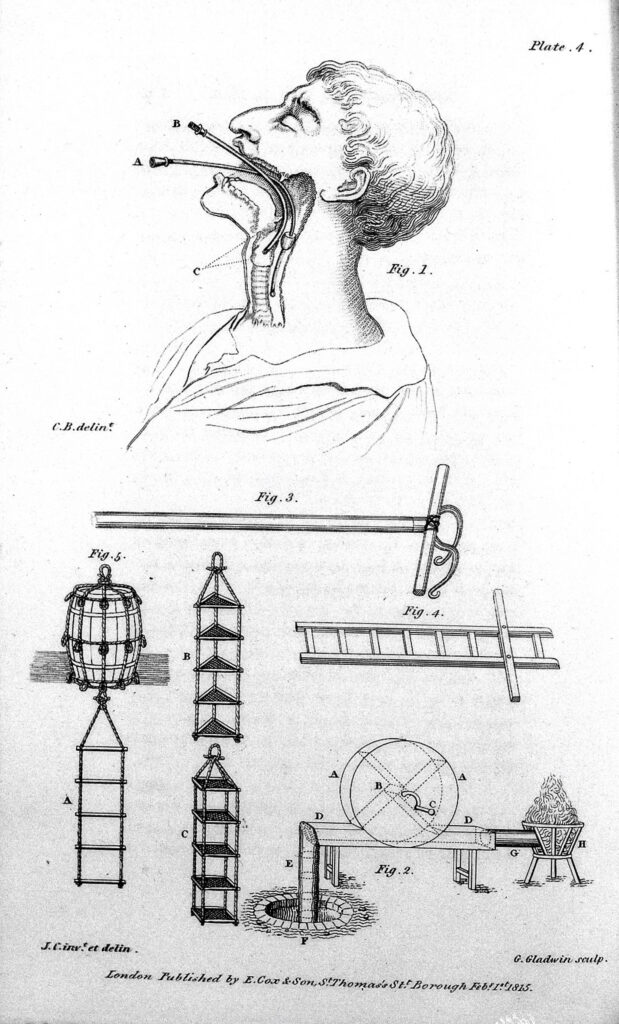

–¿Liberación? ¿Usted es médico, médico? Quiero decir que si estudio medicina.

–Sí, claro, tengo mi título de médico cirujano y una especialidad en medicina del deporte. Sé que suena raro eso de liberación. Si no fuera yo quien da este tipo de terapia, diría que es un invento para engañar a la gente. Bueno, sí es un invento mío, de cierta forma, pero no engaño a nadie. Tampoco digo que lo que hago tenga un respaldo científico, porque no he hecho los estudios pertinentes para afirmar que es un tratamiento que resuelva problemas médicos.

–Pongámoslo así: yo aplico mi conocimiento médico sobre el cuerpo humano para que la gente dé un salto de fe hacia la liberación de problemas que tengan en sus vidas personales o profesionales. O sea, combino ciencia con creencia. Aunque si somos realistas, a veces no hay mucha distinción entre una cosa y la otra.

–Mejor le describo mis procedimientos. La terapia que yo le doy a las personas consiste en producir un nivel de asfixia que produce placer. Seguramente usted ha escuchado algo de eso. Los psiquiatras lo consideran una parafilia y una práctica de riesgo, pero en mi experiencia he podido observar que se puede alcanzar un dominio que le permite a los pacientes llegar a una epifanía. Antes de empezar la terapia, analizo la complexión, el estado de salud y otros aspectos físicos del paciente para estimar qué tanto puede resistir el procedimiento, es decir, qué tanta fuerza puedo ejercer, porque mi técnica es el estrangulamiento.

–Sí, sólo utilizo mis manos y dejo que el cuerpo de mis pacientes me vaya diciendo hasta qué punto llegar. Hay quienes necesitan poco, otros mucho más, pero siempre trato de evitar ponerlos al límite de sus condiciones de salud. Al final, ellos encuentran en esta situación una forma de enfrentarse a sus problemas. El extremo al que los llevo y la vuelta en sí mismos, una vez que lograron el orgasmo, les permite ver que pueden superar aquello que los ahoga en sus vidas, y que además les puede resultar placentero. Por eso le digo que la terapia es una mezcla de saber médico y fe.